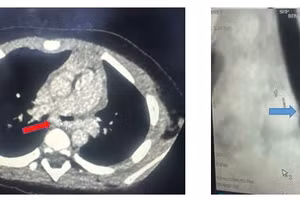

GD&TĐ - Bé gái 3 tuổi sốt cao liên tục, ho nhiều, nhập Bệnh viện Nhi Đồng Thành phố trong tình trạng suy hô hấp nguy kịch được đặt nội khí quản, thở máy.